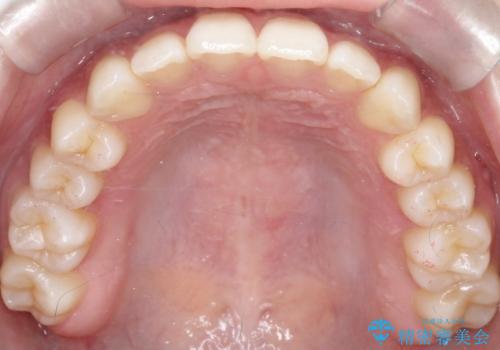

見た目、嚙み合わせ及び、治療期間や施術内容に大変ご満足いただきました。